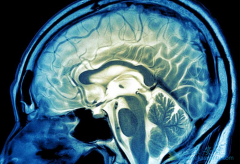

• 脑瘤的症状往往取决于颅内肿瘤的部位

脑瘤的症状往往取决于颅内肿瘤的部位

什么是脑瘤? 脑瘤的症状 有哪些?脑瘤是颅内肿瘤的简称,和其它肿瘤一样,也有良性和恶性之分。通常人们所说的“脑癌”,泛指大脑恶性肿瘤,比较常见的就是脑胶质瘤。脑瘤会造成神经系统的功能障碍,严重时会危机生命,所以脏我脑瘤的症状有助于尽早发 ...